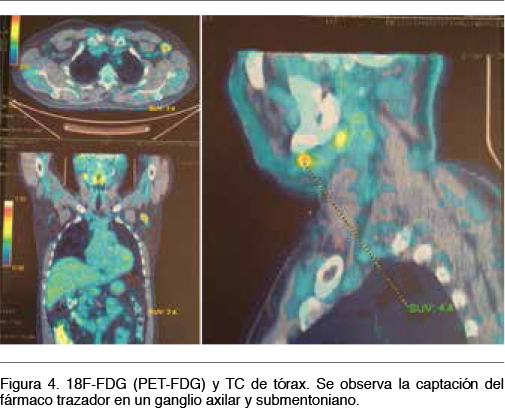

Se realiza así el diagnóstico clínico - electrofisiológico de Síndrome Miasténico de tipo presináptico y dentro de este subgrupo por sus características clínicas el de un LEMS. Se calculó un Delta p- Score de 1. Hemograma, VES y enzimograma hepático normal. PEF normal. Se solicitó Rx de tórax y tomografía de cuerpo entero. No se observan imágenes sugestivas de una neoplasia. Se realiza a continuación tomografia por emisión de positrones con 18F-FDG (PET-FDG) observando adenopatías múltiples (regiones cervicales, axilares, de mediastino y retroperineales), algunas de ellas hipermetabolicas (axilar izquierda, submaxilar derecha e inguinales bilaterales a predomionio izquierdo), donde se destaca por su tamaño y nivel de captación la axilar izquierda (Figura 4). Se envía al paciente para realización de biopsia diagnóstica del ganglio más accesible. No se realizo dosificación de los anticuerpos anti canales voltaje dependientes de calcio (VGCC tipo P/Q o tipo N) por no disponer de dicha técnica en nuestro país.